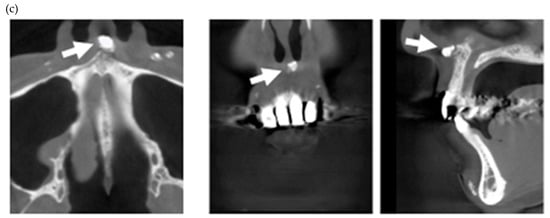

Figure 3.

Multiple external root resorption and calcinosis at the oral region in pt. 4. A dental X-ray photo and CBCT image of teeth and the deposition of calcinosis at the palatal site (a–c). The white arrowhead represents root resorption, the black arrowhead, PDL space widening, and the white arrow, calcinosis, while the black arrow shows a failure to close the space with orthodontic treatment.

In the present study, MERR was detected in four SSc patients, including one described in a case report (pt. 1) [12]. The causes of external resorption, including trauma, periodontal and periapical inflammation, orthodontic treatment, internal bleaching or tumors, were not found in the teeth having external resorption. Dental X-rays and CBCT images showed that MERR was observed in six, six, and four teeth in pts. 2, 3, and 4, respectively (Figure 1a, Figure 2a and Figure 3a). A widening PDL space was detected in all patients. A space between canines and premolars in the upper jaw was found in pts. 3 and 4 (Figure 2a and Figure 3a). Furthermore, the deposition of calcinosis in the nasal spur was noted in pts. 1, [12], 2, and 3, while calcinosis in the palatal plate was observed in pt. 4 (Figure 2c and Figure 3c).